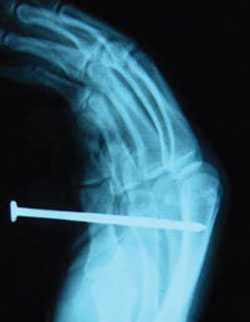

Nail guns are powerful, easy to operate, and boost productivity for nailing tasks. They are also responsible for an estimated 37,000 emergency room visits each year – 68% of these involve workers and 32% involve consumers. Severe nail gun injuries have led to construction worker deaths. Fortunately, these injuries can be prevented, and more and more contractors are making changes to improve nail gun safety. Research shows that risk of injury is twice as high using "contact" trigger nail guns compared to "sequential" trigger nail guns.

Two framers were working together to lay down and nail a subfloor. One framer was waiting and holding the nail gun with his finger on the contact trigger. The other framer was walking backwards toward him and dragging a sheet of plywood. The framer handling the plywood backed into the tip of the nail gun and was shot in the back. The nail nicked his kidney, but fortunately he recovered. As a result of this incident, the contractor switched to using only sequential triggers on framing nail guns. Co-workers can get injured if they bump into your contact trigger nail gun. You can prevent this by using a full sequential trigger.